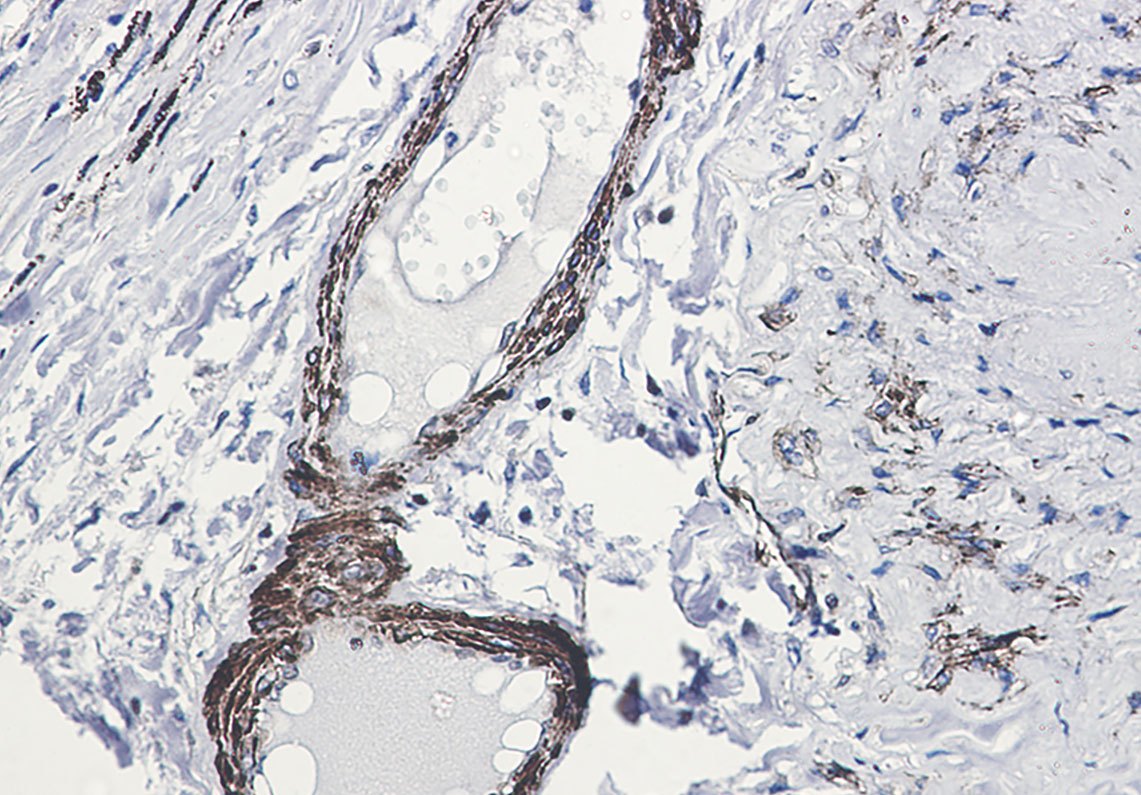

- Immunohistochemistry analysis of paraffin-embedded Human lung cancer using beta Arrestin 1 (Phospho-Ser412) antibody.High-pressure and temperature Sodium Citrate pH 6.0 was used for antigen retrieval.